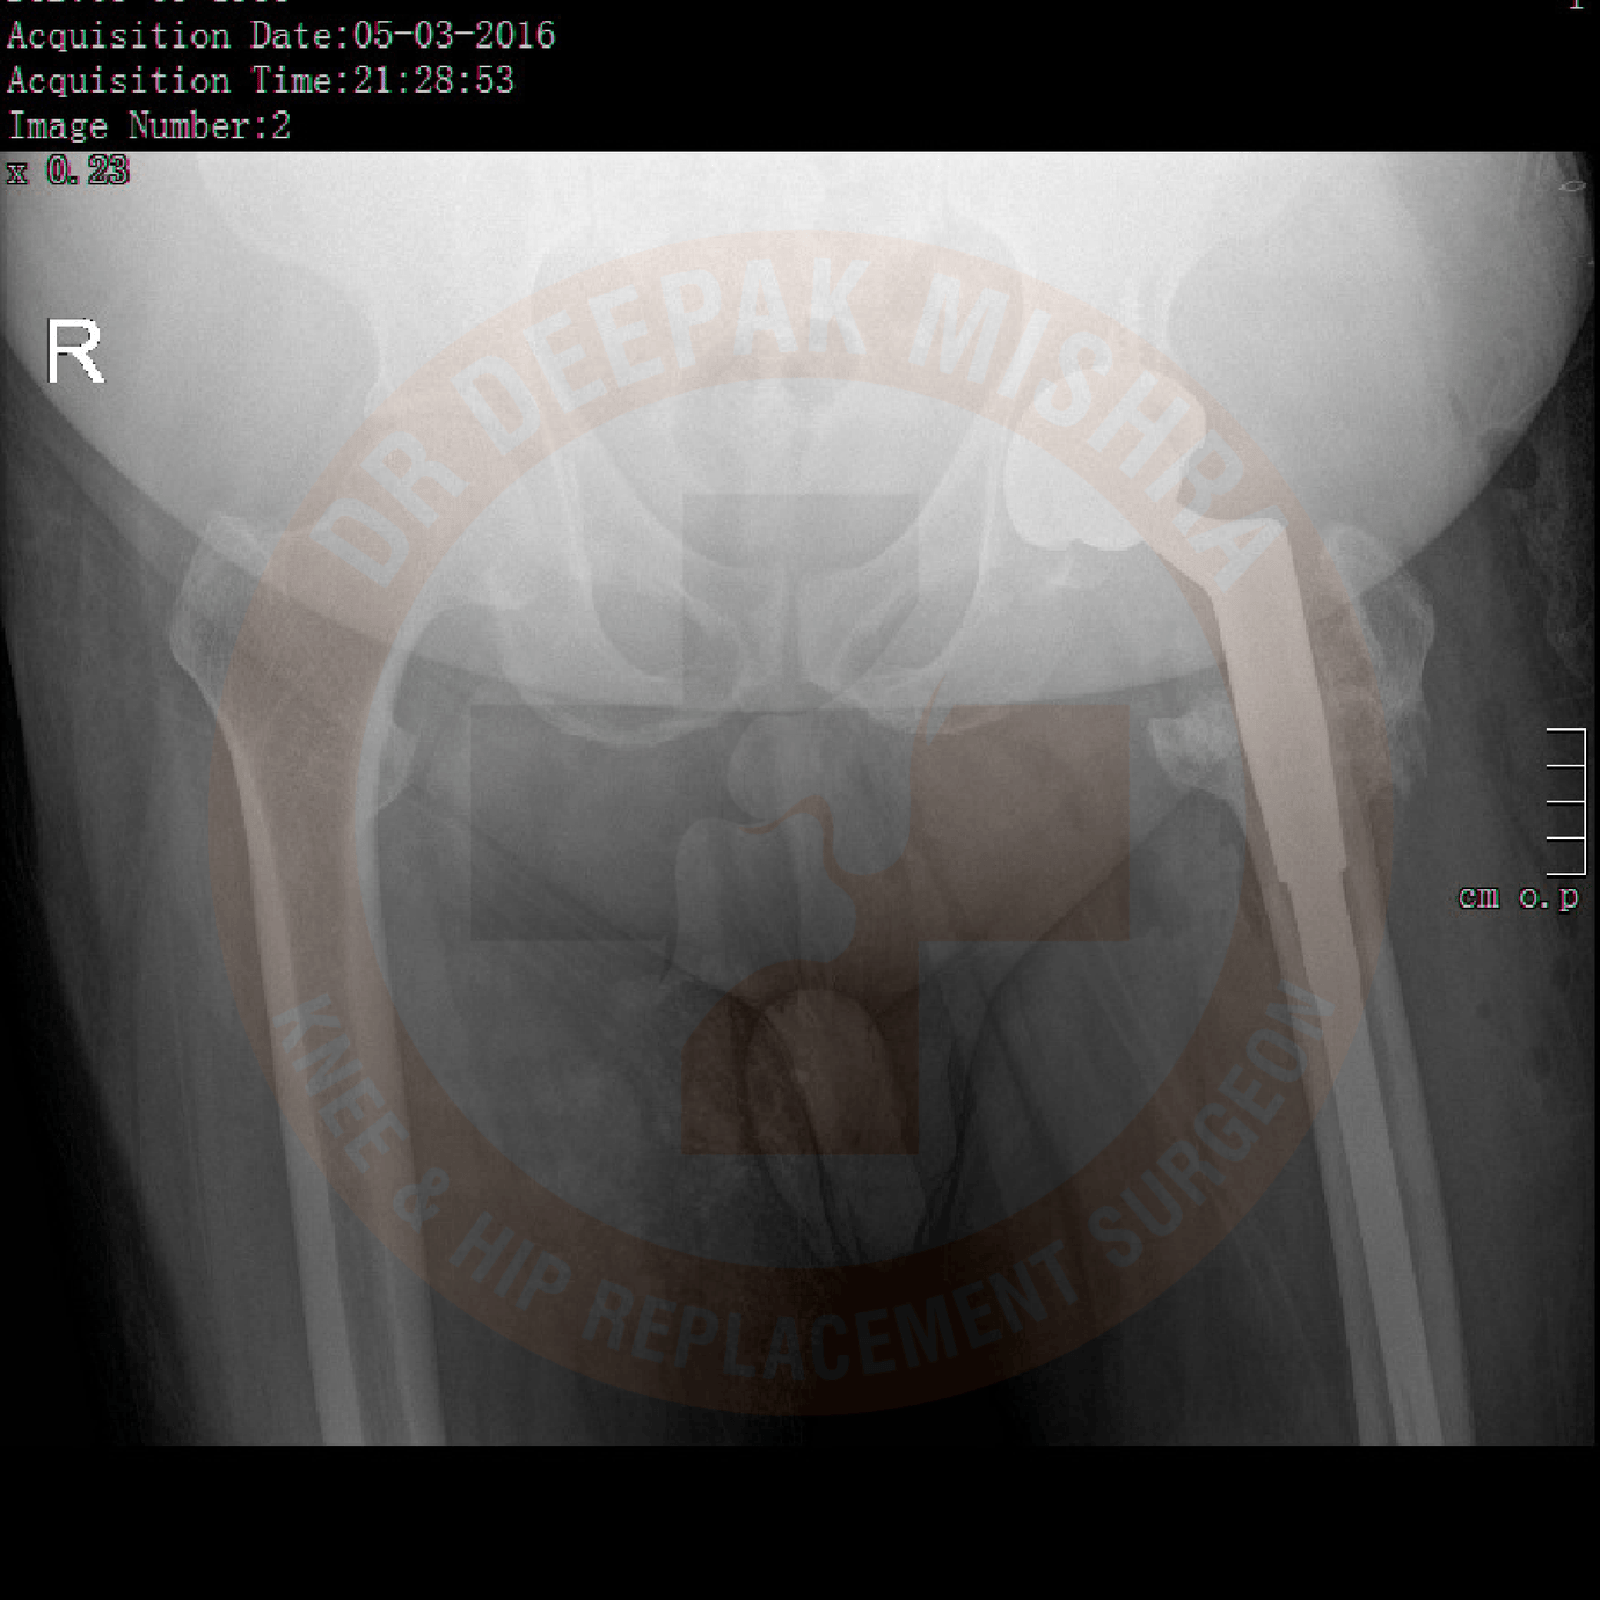

Patients with hip arthritis present with pain around their hip joint and difficulty in walking. They also have difficulty in sitting on the floor or squatting. Few patients present with complaints of not able to perform marital obligations. Detail history is taken to ascertain the underlying cause. Proper examination is performed to assess movements in the affected hip joint. Radiological and blood investigations are performed as per the requirements. MRI and CT scan (with 3D reconstruction) provided the detailed anatomical extent of disease and any associated loss of bony architecture. It is important to get as much information as possible before planning treatment options.

Your doctor will do clinical examination of hip joint, spine and other joints of your body. Radiological examination (X-rays and MRI) and blood investigations will be performed based on clinical findings. It varies from patient to patient as per their underlying problem.

In total hip replacement surgery, we remove the damaged femoral head (ball) and cartilage of the acetabulum (cup) and replace it with metal implants. During the surgery, size of the acetabulum and femoral head are measured to provide optimized size of the implant.